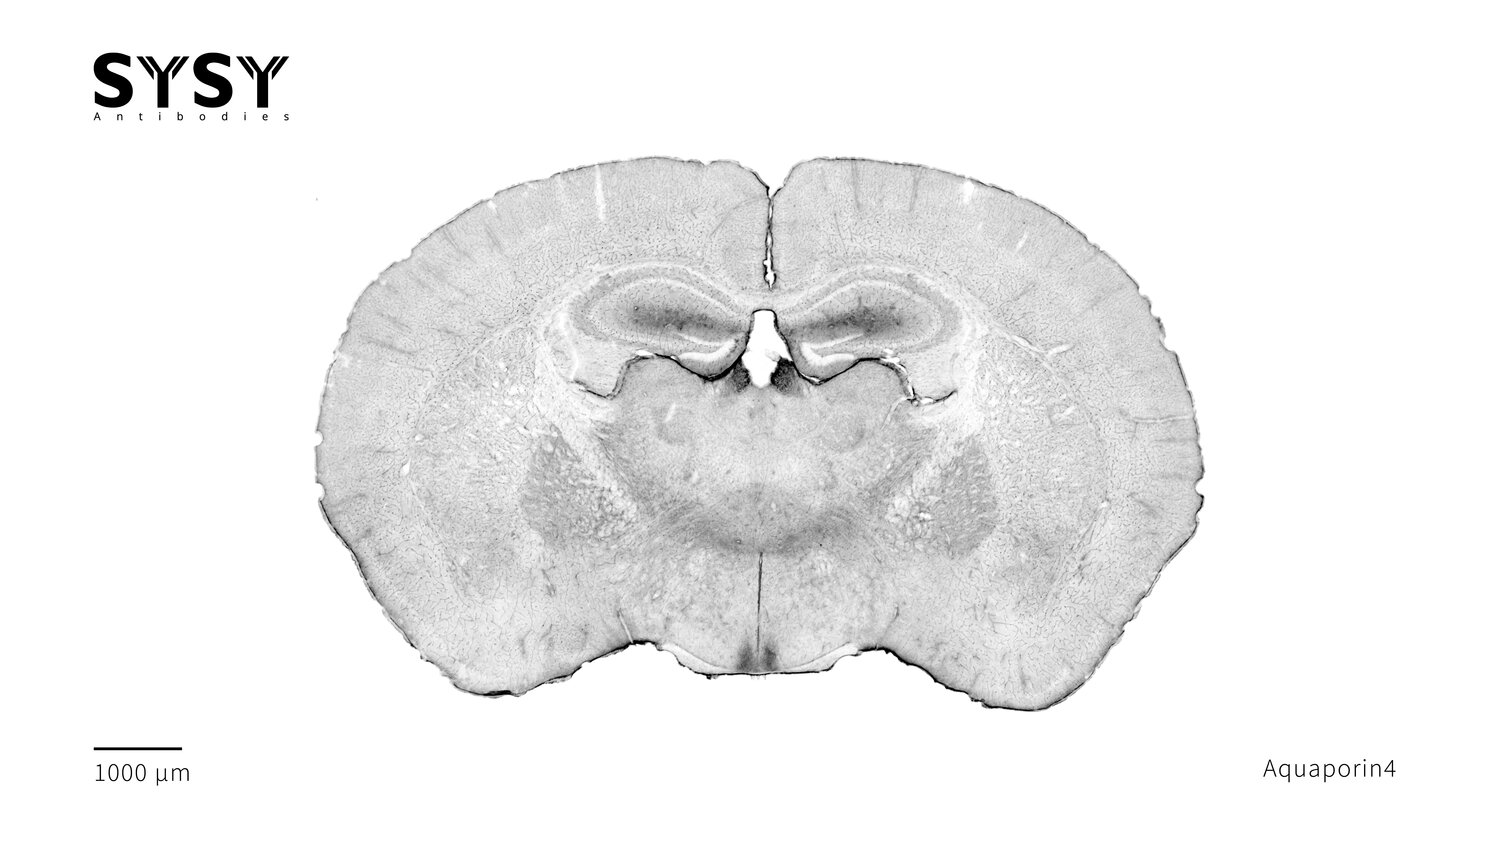

Aquaporin4

Indirect immunostaining of a formaldehyde fixed coronal mouse brain section with chicken anti-Aquaporin4 antibody (cat. no. 429 009, dilution 1 : 2000).